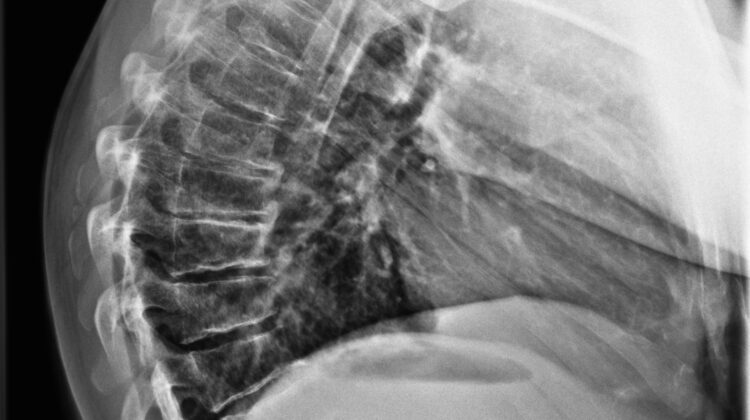

تصوير الأشعة الجانبية يهدف إلى:

قياس درجة الاعوجاج الجانبي (Cobb Angle)

تقييم التقوس الصدري العلوي والسفلي لضمان توازن الرقبة.

يقيس الطبيب شكل العمود الفقري باستخدام الأشعة الأمامية والجانبية الكاملة:

التقوس الصدري العلوي: T1–T5

التقوس الصدري السفلي: T5–T12

التقوس الكلي: T1–T12

زاوية الرقبة: لمعرفة الانحناء أو الميل للأمام

هذه القياسات تساعد الطبيب على فهم التوازن ثلاثي الأبعاد للعمود الفقري وتحديد خطة العلاج المناسبة.